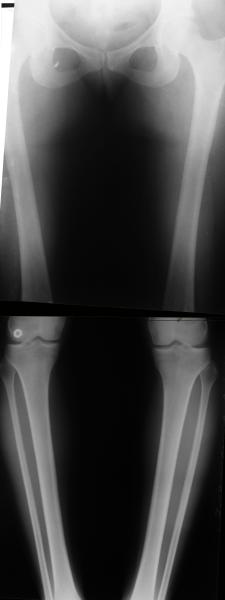

AC> Обратилась дама 25 лет. Вынуждена ходить в брюках из-за genu varum,

AC> что побудило обратиться за коррекцией.

Судя по снимку у девушки имеется внутренняя установка надколенников...

Как у нее с торсионным статусом? Бедро? Голень? КТ? Торсиометры? А то, куда будут

смотреть надколенники после вашей коррекции - тоже существенный

косметический момент. Или не так?

. On the right leg you can see some of the tools (from the tool bar above) applied to demonstrate a mild mech-axis varus of about 5 degrees.

On the left the bone landmarks used in the anlaysis are shown.

The data for the analysis are in the XLs sheet below, exported from the program automatically.

I have given a label of the abreviations and some normative values.

In essence she has a mild mech-axis varus of 7 degrees with some contribution from the femur (2) degrees and more from the tibia (6 degrees), none from the joint.

The analysis took about 6 mins.